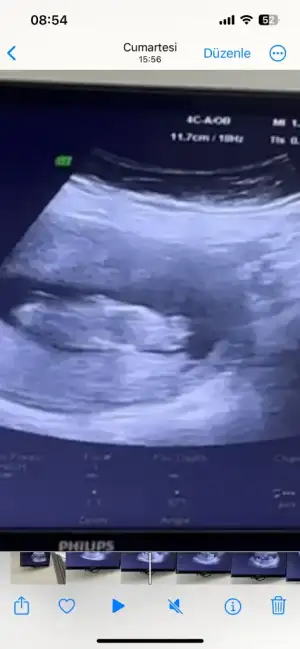

bende tahmin alabilirmiyim